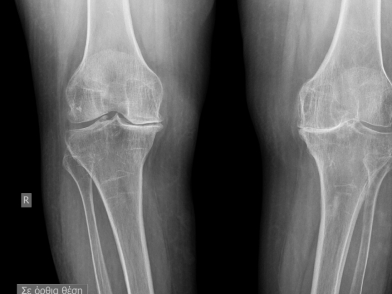

Πριν την αρθροπλαστική, θα υποβληθείτε σε έναν πλήρη προεγχειρητικό έλεγχο. Αυτός περιλαμβάνει αιματολογικές εξετάσεις, καρδιολογικό έλεγχο (ΗΚΓ, υπέρηχος καρδιάς αν απαιτείται), ακτινογραφία θώρακος και εξειδικευμένες ακτινογραφίες του γόνατος (και συχνά ολόκληρου του ποδιού) για την ψηφιακή προσομοίωση και τον ακριβή υπολογισμό των διαστάσεων των εμφυτευμάτων.

Ένα από τα σημαντικότερα βήματα. Εάν το γόνατό σας είναι “στραβό” (προεγχειρητική ραιβότητα ή βλαισότητα), αυτό πρέπει να διορθωθεί απολύτως. Αν παραμείνει παραμόρφωση, τα υλικά θα φορτίζονται ασύμμετρα και θα χαλαρώσουν γρήγορα. Για να επιτευχθεί η ευθυγράμμιση, η οστεοτομία (το κόψιμο του φθαρμένου οστού) της κνήμης γίνεται αυστηρά κάθετα στον επιμήκη άξονα της κνήμης, ενώ το κάτω πέρας του μηριαίου κόβεται σε συγκεκριμένες μοίρες. Στόχος είναι ο μηχανικός (εκτατικός) άξονας να περνά ακριβώς από το κέντρο της άρθρωσης (το μεσοσπονδύλιο έπαρμα της κνήμης).